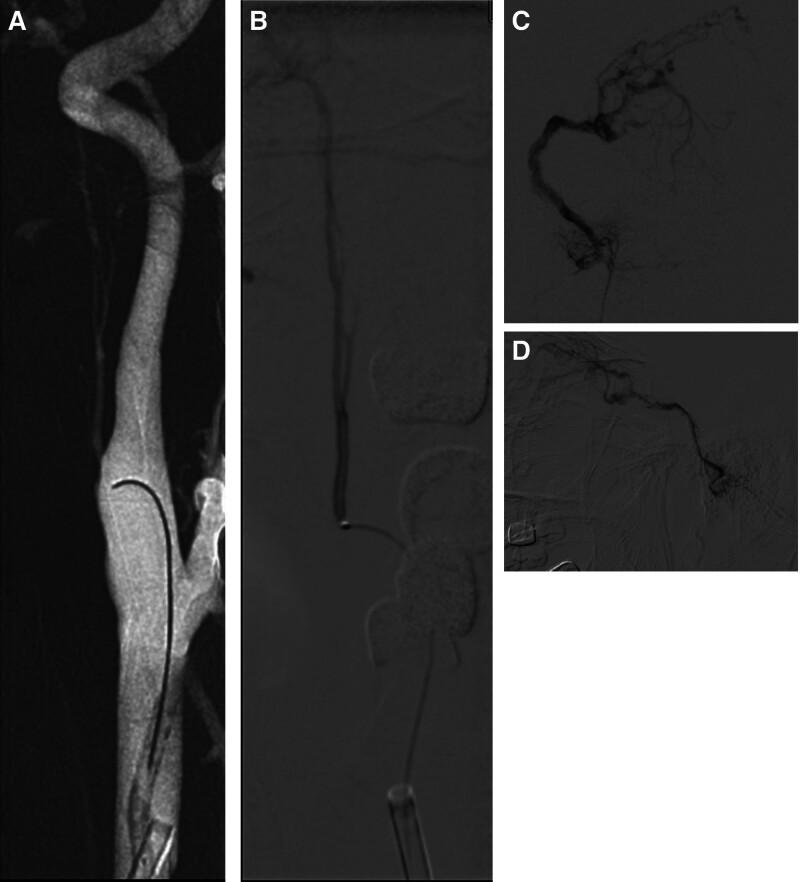

A digital subtraction angiography examination revealed a JFDAVF, which showed the feeding artery is ascending pharyngeal artery, with retrograde flow through the inferior petrosal sinus into the ophthalmic vein.

An endovascular interventional therapy method was chosen, Marathon microcatheter in synchro-10 Microguide wire auxiliary super selected to ascending pharyngeal artery, about 0.3 mL of 13% concentration GLUBRAN was injected with a Marathon microcatheter, post-embolization angiography confirmed obliteration of the fistula site.

Aspiration when drinking and hoarseness after endovascular embolization, after 3 days, the eye symptoms completely disappeared. after 3 months, no aspiration observed while drinking and normal articulation. the patient recovered well post-embolization.